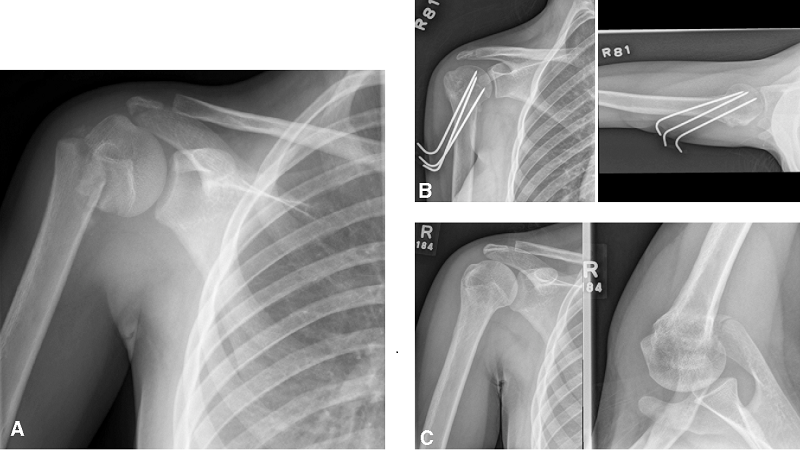

Để chẩn đoán cận lâm sàng đối với các trường hợp gãy đầu trên của xương cánh tay, các chuyên gia y tế thường sử dụng xét nghiệm X-Quang. Khi tiến hành, bác sĩ sẽ thực hiện việc chụp chiếu với nhiều tư thế khác nhau:

Điều trị phẫu thuật được chỉ định cho những ca có mức độ thương tổn nặng (gãy rời, dập vỡ, lệch khớp mạnh,...). Tuy nhiên trước khi thực hiện, bác sĩ cần phải thực hiện nhiều xét nghiệm để đánh giá sức khỏe và khả năng đáp ứng điều trị của người bệnh. Cụ thể, họ sẽ đo lường lượng máu nuôi, chất lượng xương để xem bệnh nhân có thể phục hồi sau phẫu thuật được hay không.

Các phương pháp phẫu thuật phổ biến thường được áp dụng bao gồm: Mổ xuyên đinh, kết xương bằng đinh nội tủy, kết xương bằng nẹp vít thường hoặc nẹp vít khóa, thay khớp vai nhân tạo,...